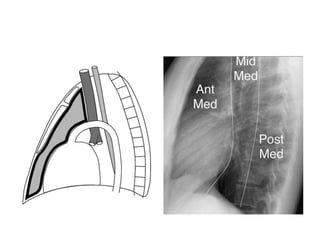

• Felson’ method - line extending from the diaphragm to the

thoracic inlet along the back of the heart and anterior to the

trachea separates the anterior and middle mediastium.

• A line that connects points 1 cm behind the anterior margins

of the vertebral bodies separates the middle and posterior

mediastinal compartments.